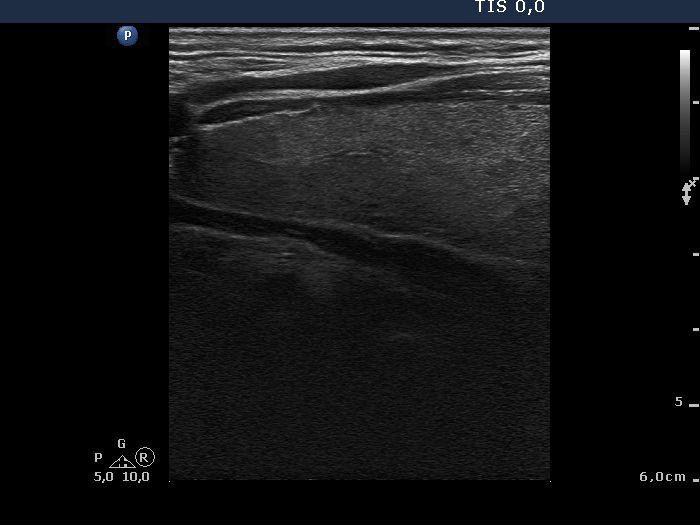

Ultrasonography: The thyroid was echonormal with a few insignificant lesions. There was a large cystic lesion dorsal to the lower third of the right lobe.